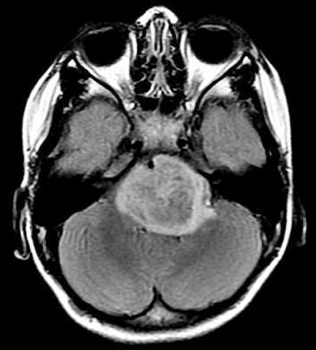

È stato annunciato come un possibile candidato per il trattamento di uno dei tumori cerebrali infantili più aggressivi, il glioma pontino diffuso, che colpisce bambini da 4 a 9 anni. Il composto panobinostat (LBH589), già in uso nel trattamento di diverse forme tumorali, è stato identificato in uno studio multicentrico appena pubblicato sulla rivista Nature Medicine.

Che cosa c’è alla base della malattia: il glioma pontino diffuso

Il glioma pontino diffuso, con una mortalità che a cinque anni raggiunge il 100%, è la principale causa di decessi per tumore cerebrale in età pediatrica ed «è il secondo tumore cerebrale infantile più diffuso». I pazienti perdono il controllo dei muscoli e i sintomi si sviluppano rapidamente e sono devastanti «perché il tumore è localizzato in una struttura critica del cervello situata nel tronco encefalico, il ponte, costituito prevalentemente da fibre di connessione tra il cervello e la colonna spinale. Il tumore è infiltrante, ovvero si insinua nel tessuto cerebrale sano, e non è quindi aggredibile chirurgicamente». Quindi, il trattamento usualmente è limitato alla sola radioterapia e chemioterapia, senza neppure effettuare la biopsia.